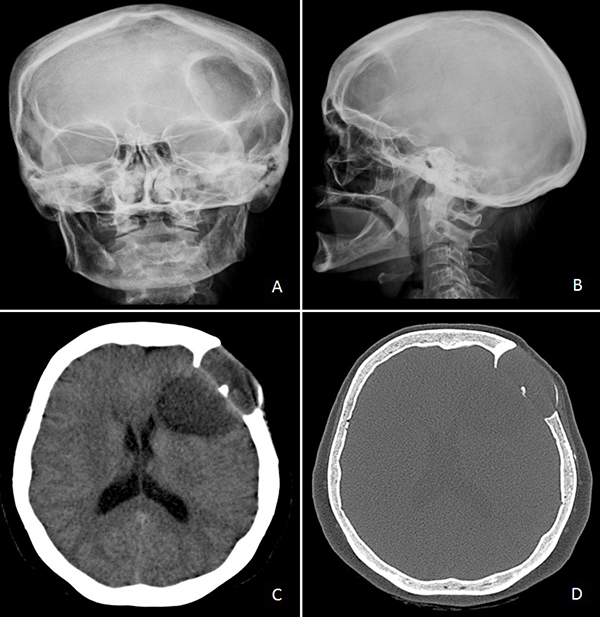

Concurrió con una radiografía (Rx) de cráneo frente y perfil donde se evidenció una lesión radiolúcida, circular y de bordes definidos con signos de remodelación esclerótica (Figura 1A y B). Tomografía computada (TC) de encéfalo mostró una lesión lítica de calota con deformación y esclerosis de la misma asociada a compromiso subgaleal, invasión intradural y extensión intraparenquimatosa en imagen de “reloj de arena” (Figura 1C y D).

Figura 1. A) y B) Rx de cráneo frente y perfil. C) y D) TC de cerebro sin contraste endovenoso.

Cushing fue el primero en describir la primera característica radiológica del epidermoide intradiploico como “áreas focales de osteólisis acompañado de un margen liso generalmente esclerótico”.16 Radiológicamente se caracterizan por áreas líticas con erosión y expansión de las tablas internas y externas del cráneo con bordes escleróticos definidos y calcificados.3 Su imagen típica consta de una lesión con un diámetro menor a 5cm con bordes escleróticos, siendo atípico aquellos que carecen de tales bordes o de un tamaño mayor.13 En la TC de cerebro se describe una masa hipodensa, homogénea y lobulada, la cual no realza tras la administración de contraste endovenoso.2,13,17 Suelen presentar un rango de densidad de -20 a +20 unidades de Hounsfield (UH); en algunos casos pueden mostrar calcificaciones en la pared quística.3 En nuestro paciente, la densidad tumoral se mostró entre -3 UH y +30 UH (excepto en algunas áreas calcificadas). Estas lesiones son hipodensas debido a la combinación de colesterol de baja densidad.18 Sin embargo, la densidad tomográfica puede aumentar tornándose similar a la del líquido cefalorraquídeo (LCR) debido al mayor contenido proteico, cálcico o de detritus celulares.3,11